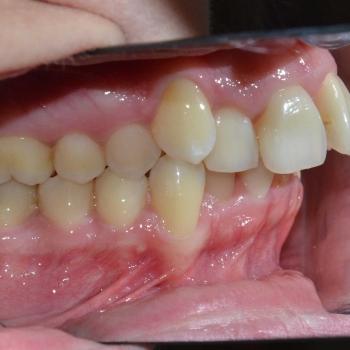

Tünde a felső fogív torlódása, illetve az alsó metszőfogak között található rések miatt keresett fel. Az első találkozásunk alkalmával azonban fény derült a középvonalak eltolódására, enyhe mélyharapásra, a felső metszőfogak túlzott elülső pozíciójára, illetve a régóta hiányzó alsó 6-os fog helyének beszűkülésére is, így a kezelési terv ezen problémák megoldására is kitért.

Tünde végül úgy döntött, hogy nem csak az esztétikai, de a funkciós problémák is szeretné megoldani, melyhez hagyományos fém fogszabályozót választott. A fogszabályozáshoz különböző kiegészítőket is igénybe vettünk úgy, mint harapásemelő, különböző intermaxillaris gumihúzások, illetve egy speciális szájpadi mini-implantátum a hozzá kapcsolódó transpalatinalis ívvel (hibrid transpalatinal ív), ami minimalizálta a hátsó fogak mozgását, miközben a felső metszőfogak hátrafele mozogtak.